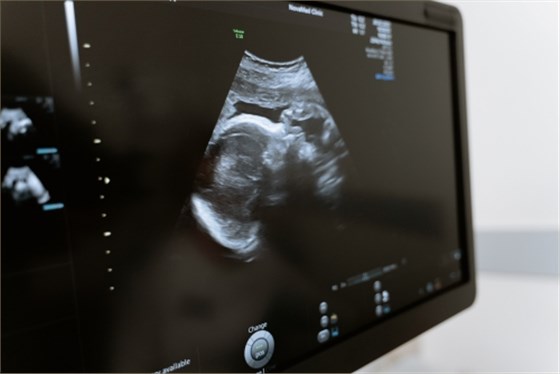

無創(chuàng)超聲通常是指無創(chuàng)DNA產前檢測技術,能檢查出胎兒是否存在染色體異常的情況,而染色體異常包括染色體結構、數目異常、基因突變等。

1、染色體結構:無創(chuàng)DNA產前檢測技術能檢查出胎兒是否存在染色體異常,其原理為通過抽取孕婦的外周血,提取母體外周血漿中游離DNA片段,利用新一代DNA測序技術進行測序,將測序結果進行生物學信息分析,進而檢測胎兒的染色體,如果存在染色體異常,則可被檢測出來;